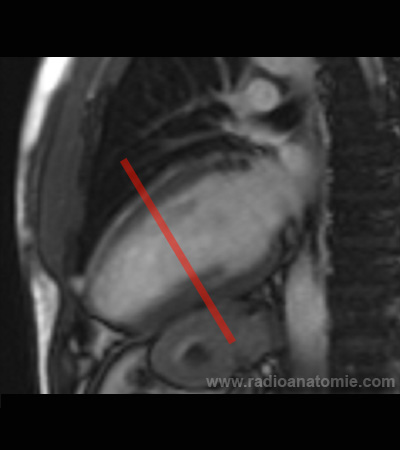

Radioanatomie et plans de coupe en IRM cardiaque

Plan petit axe